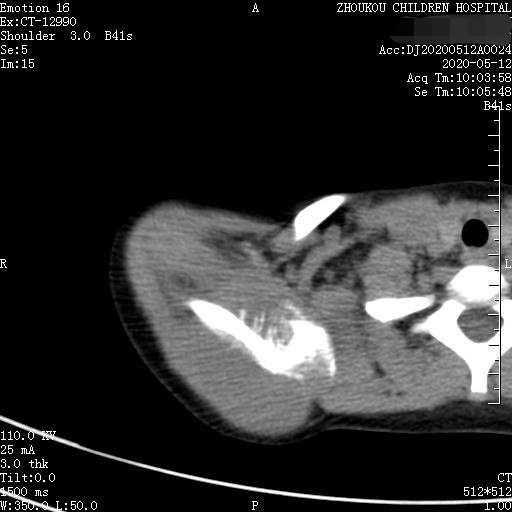

通过CT平扫发现:右侧肩胛骨骨质密度不均,骨质内可见“虫食样”低密度影,骨质边缘可见多发放射状骨针,呈“日光射线征”。周围软组织明显肿胀,肌间隙模糊。CT检查意见:考虑:右肩胛骨占位,骨肉瘤可能,不除外其它恶性肿瘤病变,请结合临床及相关检查注意复查。 影像鉴别诊断:骨肉瘤是指起源于骨间叶组织,遗留形成骨细胞直接形成骨样组织为特征的恶性肿瘤,是比较常见的骨恶性肿瘤,好发于十到二十岁青少年,骨肉瘤常见于管状骨,股骨远端胫骨近端最多见,表现为疼痛局部肿胀运动障碍,实验室检查都有碱性磷酸酶升高。

二、根据骨质破坏和肿瘤骨的多少,骨肉瘤可以分为三型,液化型以肿瘤新生骨为主,溶骨型是以骨质破坏为主,混合型新生骨的形成和骨质破坏并存,x线表现是不规则的骨质破坏伴浸润,可见日光样和放射状骨膜反应,骨膜新生骨在破坏可形成考特曼三角,骨内可见云状、絮状、针状、放射状肿瘤骨伴软组织肿块而形成。

三、常需要鉴别的诊断是骨转移瘤,年龄比较大再就是慢性化脓性骨髓炎病程比较长,好发于长骨骨干。